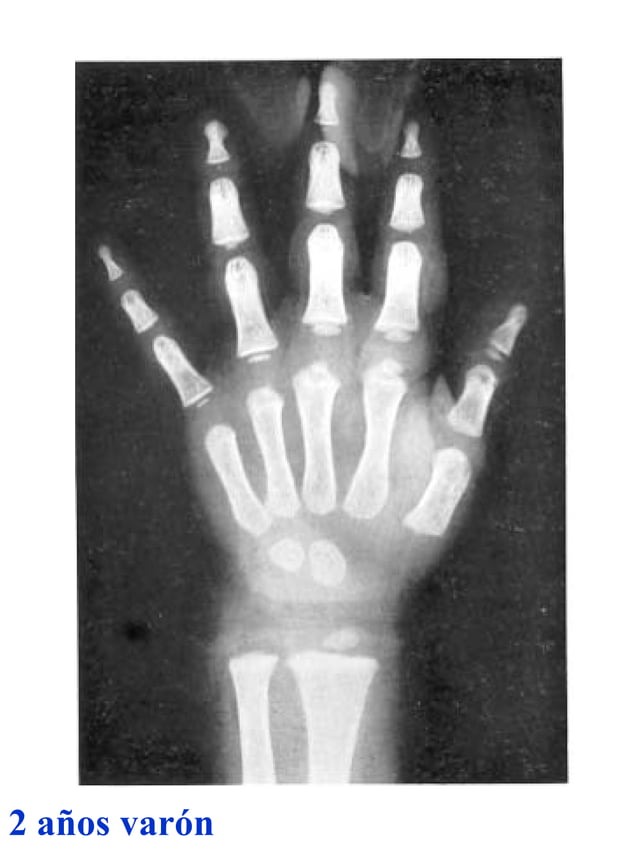

Figura 2 Imágenes de radiografías de mano y muñeca izquierda del

Figura 2 Imágenes de radiografías de mano y muñeca izquierda del Tablas De Greulich Y Pyle Edad Osea The greulich and pyle atlas is used to estimate the age of children and adolescents. El método de greulich y pyle(1) es un método simple de valoración de la edad ósea en pacientes pediátricos. El diagnóstico y la clasificación se basan en el examen físico, el análisis del crecimiento, la maduración ósea, la ecografía de útero y gónadas, y los. Tablas De Greulich Y Pyle Edad Osea.